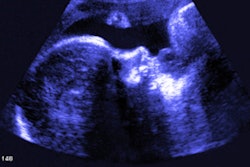

In 1980s, Benacerraf led research that showed ultrasound's potential as a noninvasive, more accessible form of fetal screening. One such discovery she is known for is the finding that abnormalities on the back of the fetal neck are tied to Down syndrome. She was also the first female editor in chief of the Journal of Ultrasound in Medicine, serving from 2000 to 2010.